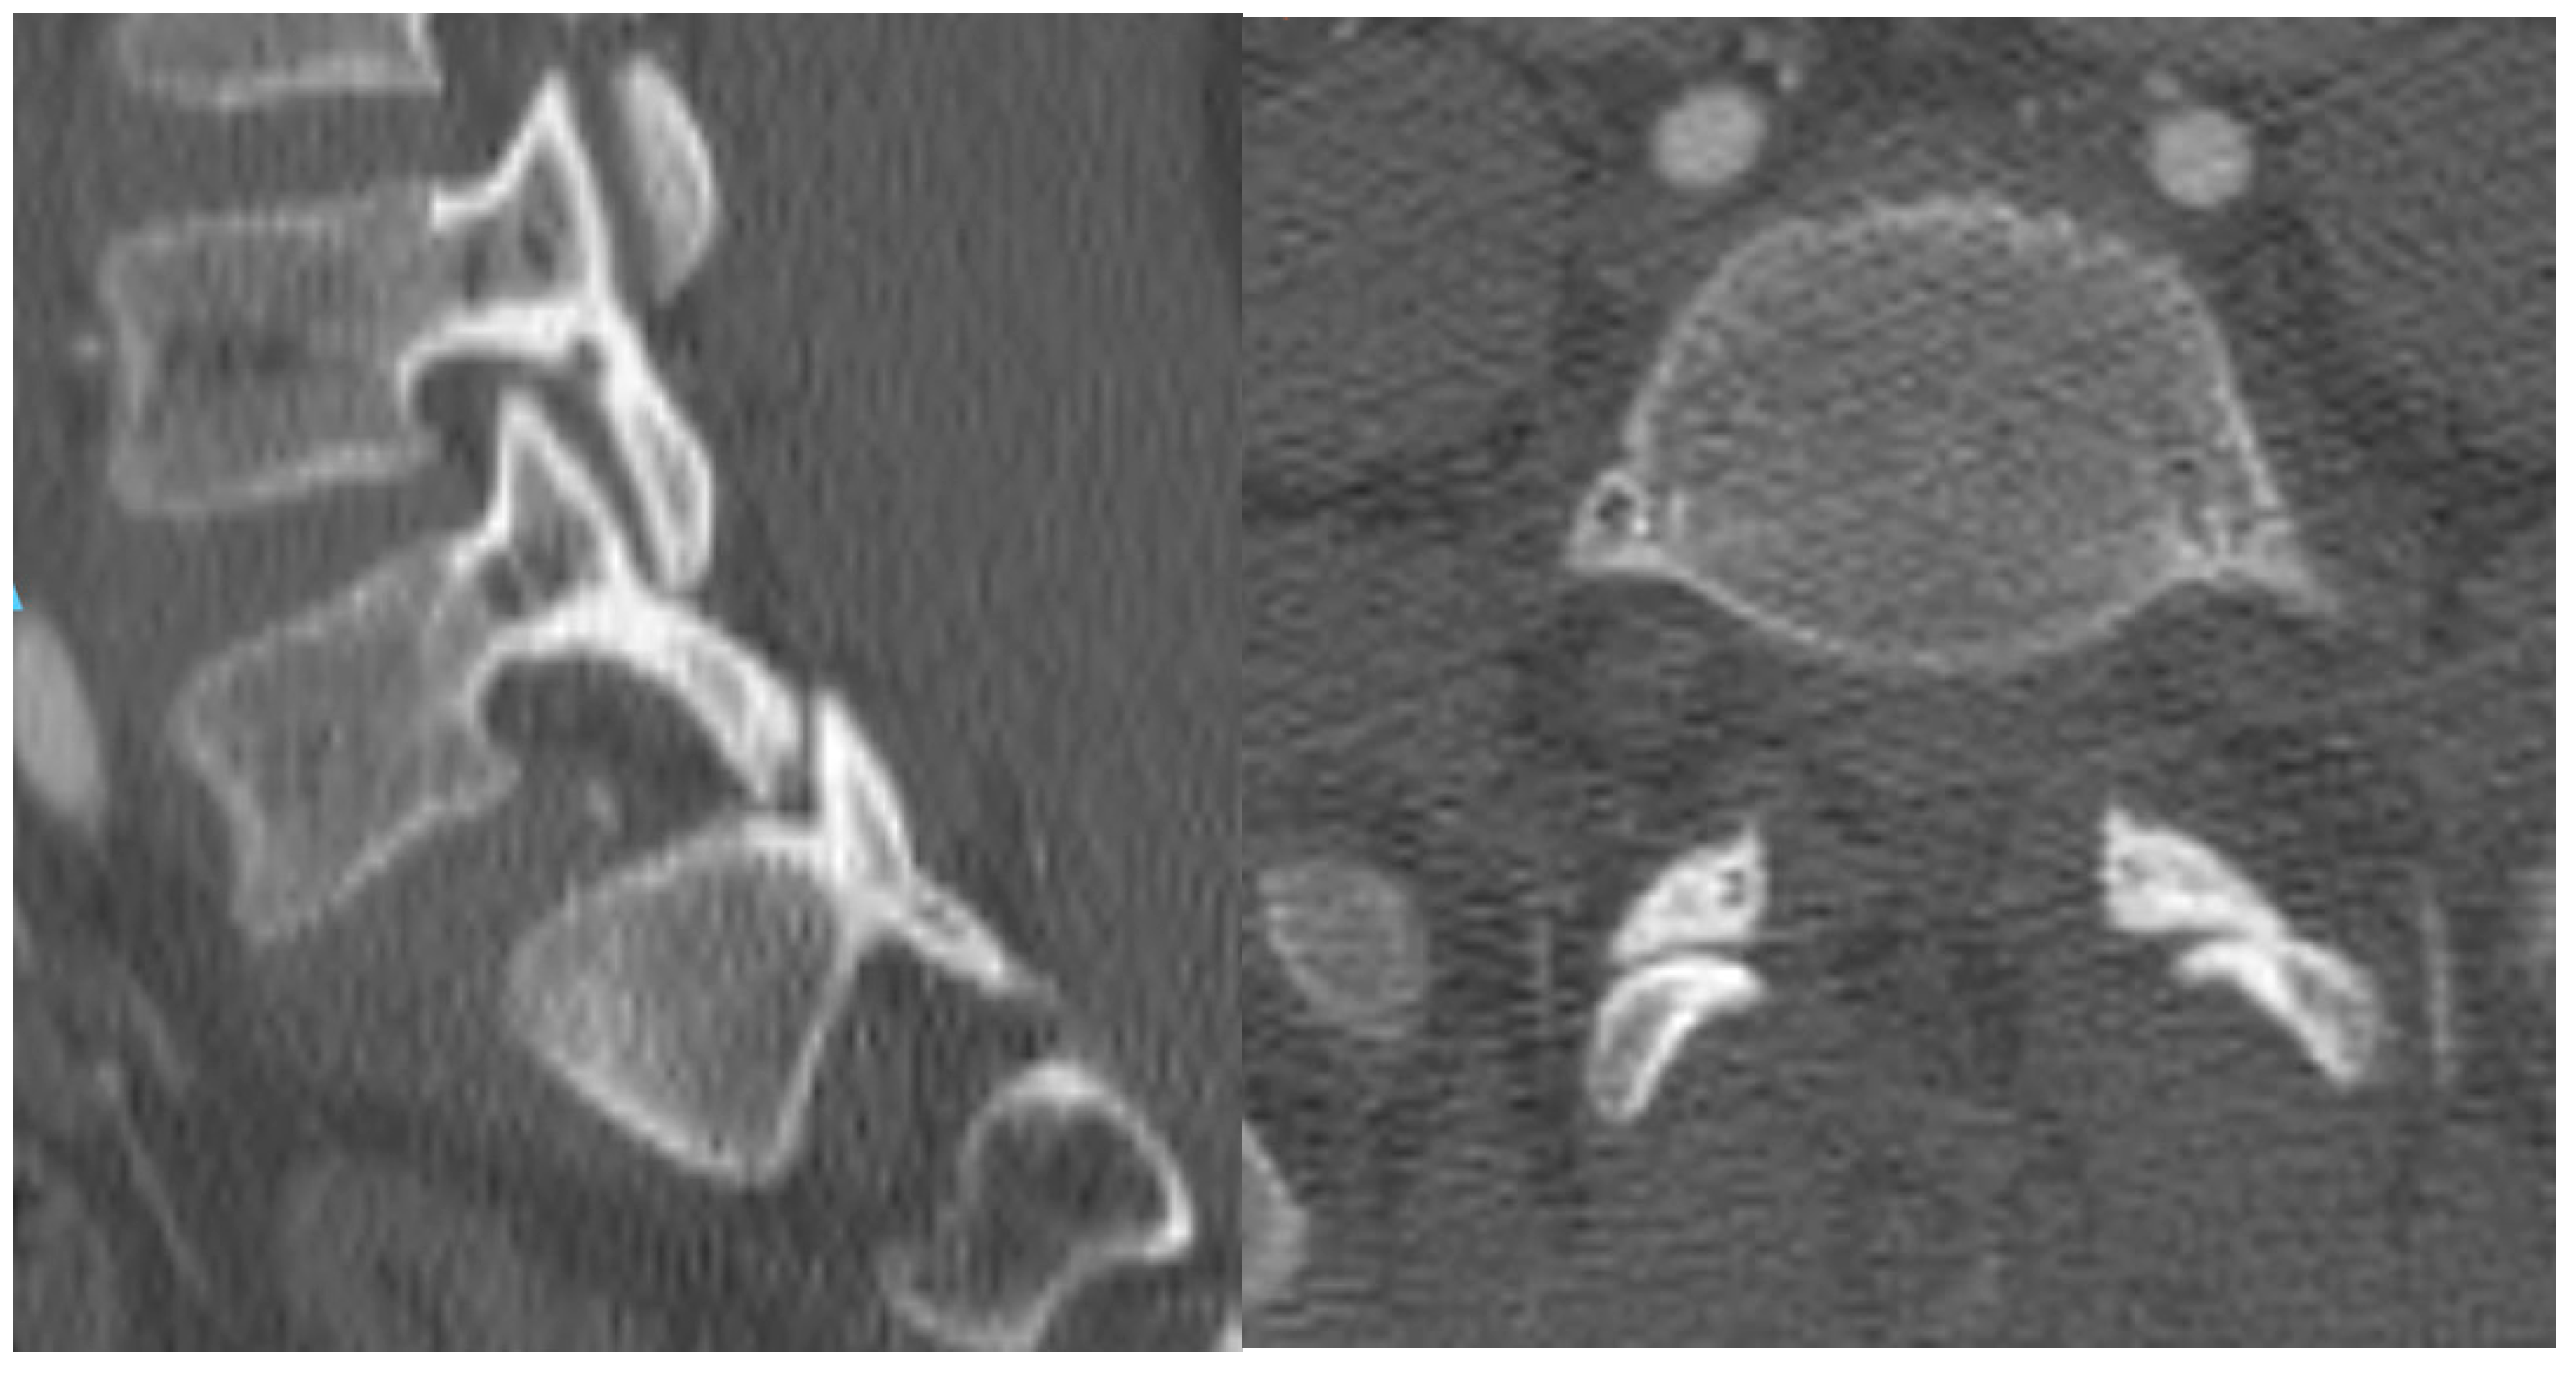

3. Case Report